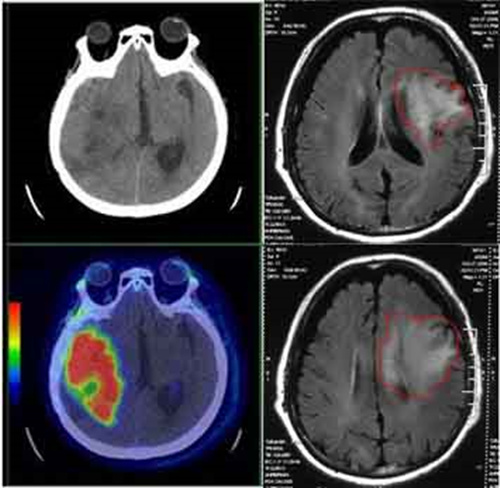

CT虽然有些辐射,但是现在头痛难忍的情况更加紧急!最终头颅CT揭示了答案:脑部胶质瘤!

在患者的大脑里不仅存在着一个可能是胶质瘤的东西,而且已经出现了脑水肿,所以患者才会突然出现头痛呕吐!